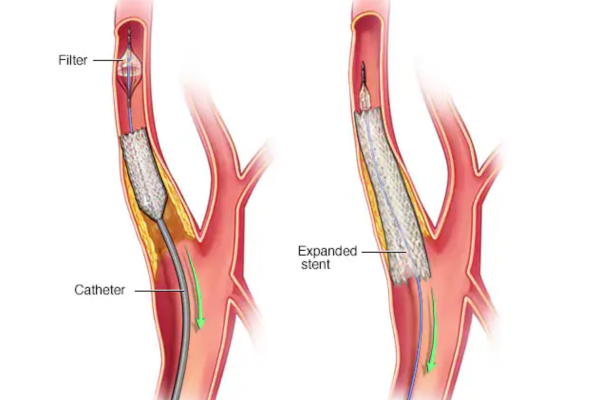

Opens narrowed arteries supplying the brain, improving blood flow and reducing stroke risk through a precise, minimally invasive procedure.

Carotid and vertebral artery stenting is a minimally invasive procedure used to treat narrowing of arteries supplying blood to the brain, which significantly increases stroke risk. Symptoms may include dizziness, weakness, or transient vision loss.

A stent is placed to widen the artery, restore smooth blood flow, prevent future strokes, and improve long-term brain circulation safely.